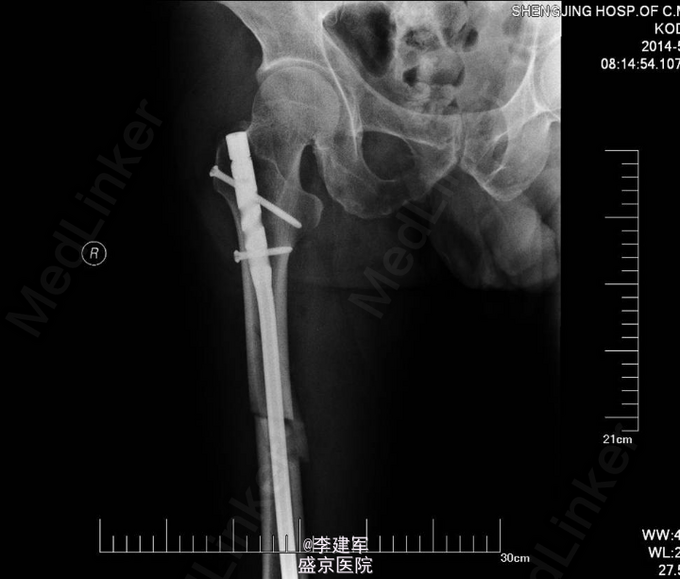

主诉:摔倒后右大腿疼痛肿胀活动受限5小时 现病史:患者家属自述骑自行车自行摔倒,摔倒后右大腿疼痛肿胀,活动受限,伤后患者昏迷约一小时,急诊送入当地医院,DR(当地医院)提示右股骨干骨折,当地医院给予患肢皮牵引固定等对症治疗。今日患者为求进一步手术治疗来我院治疗。门诊以“右股骨干骨折”为诊断收入院。患者病来一般状态可,生命体征平稳,无发热,饮食睡眠可,二便正常。

专科查体:患者平车推入病房,右下肢短缩屈曲中,右大腿疼痛,肿胀明显,可触及反常活动及骨擦感,纵向叩击痛阳性。右大腿外侧可见皮肤瘀斑,右足背动脉搏动正常,足趾活动可,皮肤感觉较健侧无明显异常。

诊断:右股骨干粉碎性骨折 患者右股骨干粉碎性骨折,拟行右股骨干骨折闭合复位内固定术。

长骨的干的骨折,行髓内针闭合复位,有助于患者早期下地行走,且创口小。粉碎性骨折不破坏骨膜,骨的血运未破坏。扩髓相当于髓内植骨,有利于生长。所以本次手术行髓内针闭合复位。